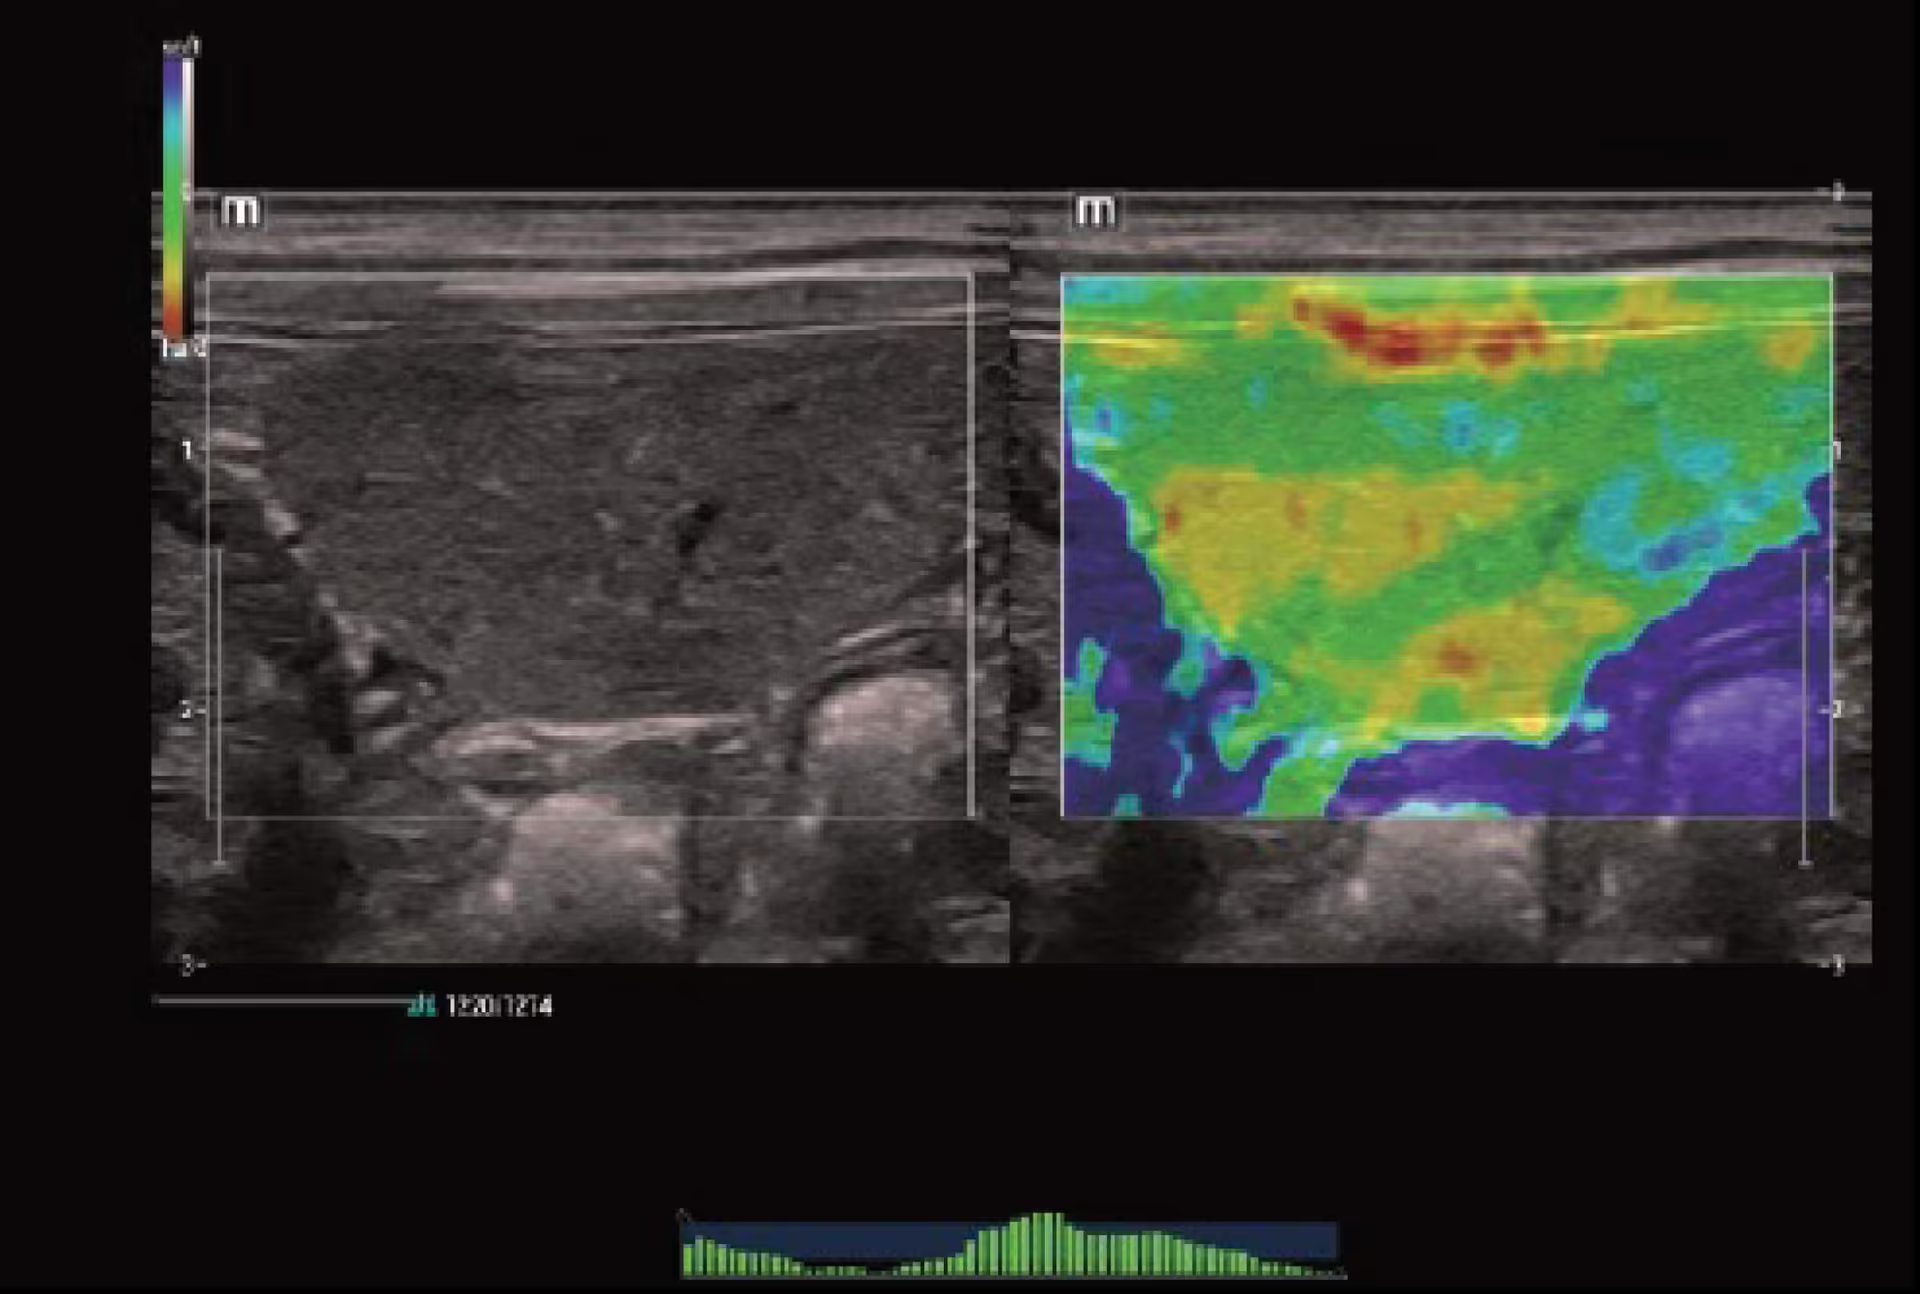

Strain Elastografi (NTE), Dalak, Köpek

Strain Elastografi (NTE), Dalak, Köpek